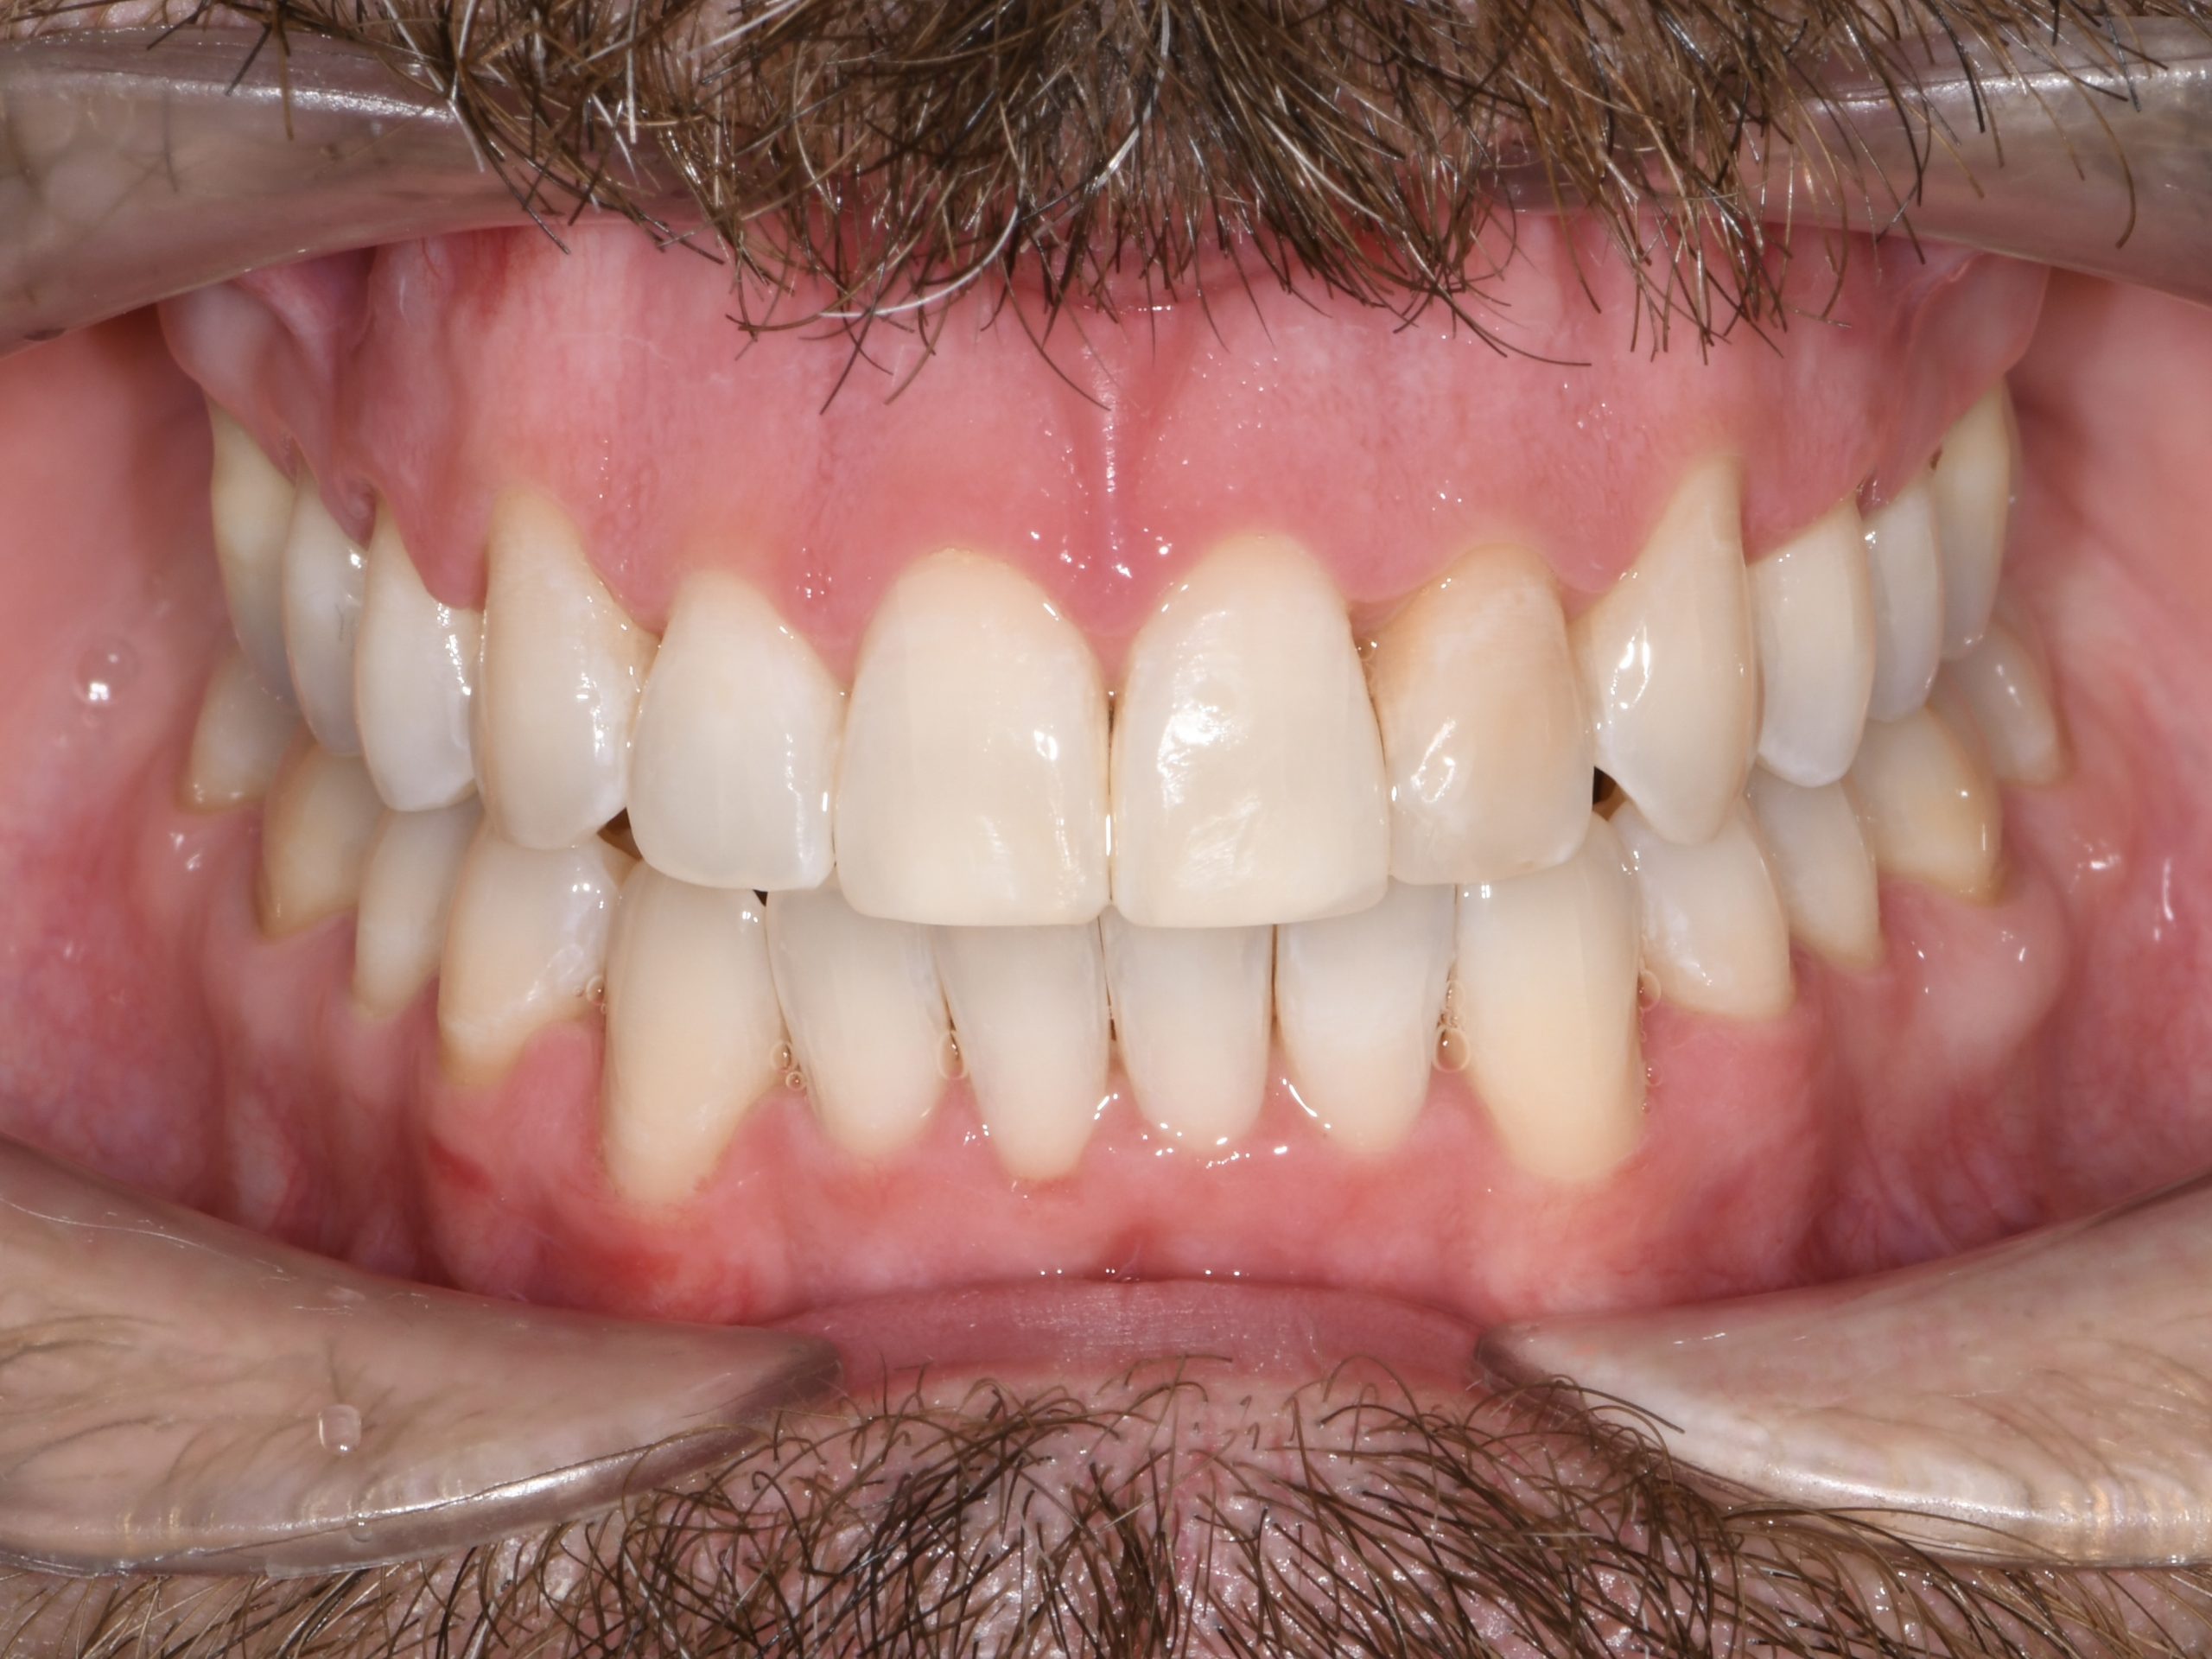

Az elmúlt évekből rengeteg szakmai referenciát tudnánk bemutatni, amelyek különböző fogszabályozási problémákat oldottak meg. Válogatva a több száz esetből, ezen az oldalon olyan képeket, információkat igyekeztünk bemutatni, amelyeknek a segítségével a jövőbeni pácienseinknek azt tudjuk üzenni: A Te fogsorod is lehet gyönyörű!

(Képeket a Pácienseink külön írásos beleegyezésével mutatjuk be!)